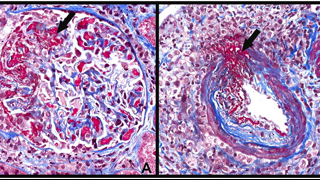

HPI- A 52-yr-old Hispanic man was found to have antineutrophil cytoplasmic autoantibody (ANCA)– associated microscopic polyangiitis with both renal and pulmonary involvement. He is treated with oral prednisone and cyclophosphamide. The prednisone is tapered and discontinued after 4 mo, and azathioprine is substituted for cyclophosphamide at 6 mo. His initial serum creatinine was 4.1 mg/dl, and it decreased to a nadir of 1.0 mg/dl after 6 mo of therapy. UA shows resolution of microscopic hematuria and proteinuria. He is now seen for a follow-up examination 2 yr after the initial diagnosis. He is asymptomatic.

LABS - Urinalysis reveals 4 to 5 erythrocytes per high power field, and no proteinuria. The serum creatinine is still 1.0 mg/dl. The erythrocyte sedimentation rate is 20 mm/h (Westergren method). An ANCA test performed 1 wk ago was significantly positive with a titer of 1:128. Previous values have been intermittently positive at low titer.